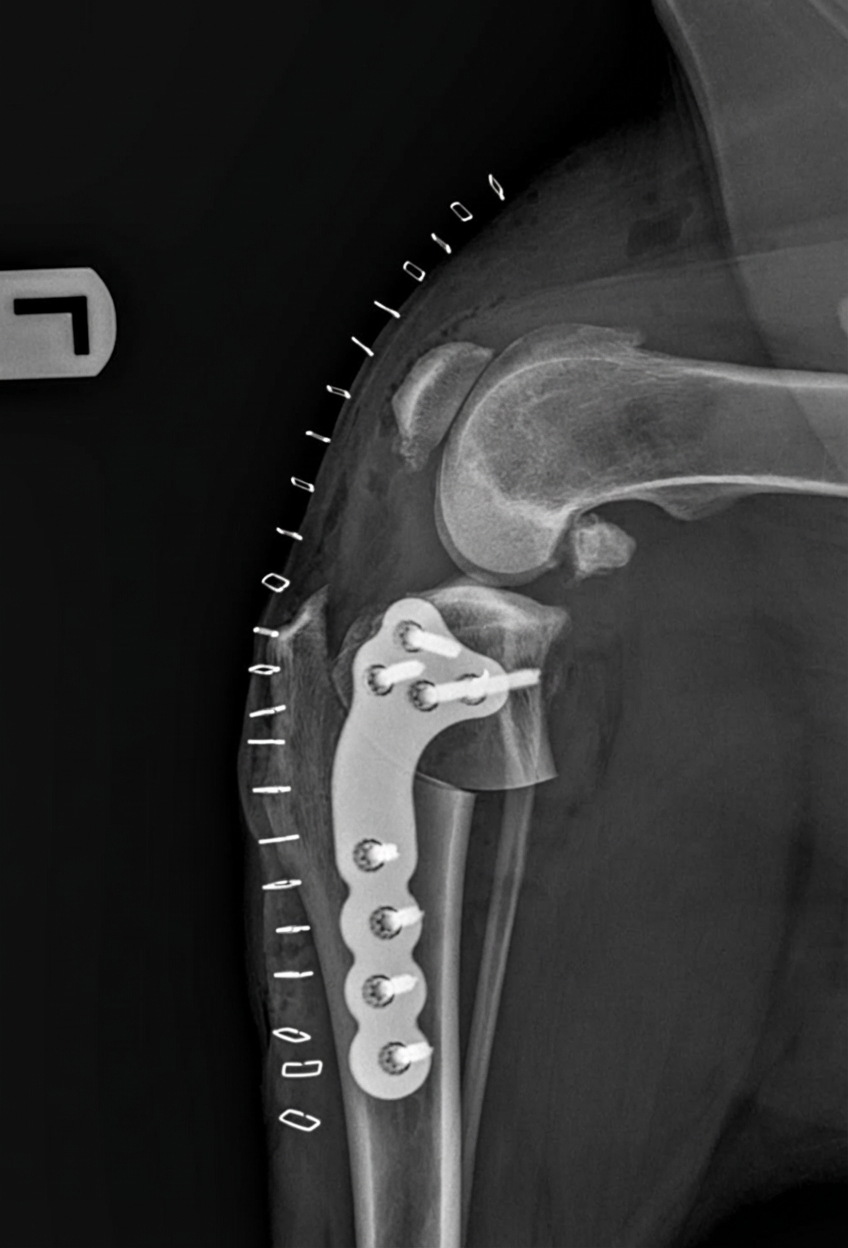

TPLO (Tibial Plateau Leveling Osteotomy) is a surgery used to treat a torn cruciate ligament in a dog’s knee.

Instead of replacing the damaged ligament, the surgeon cuts and rotates the top of the shin bone (tibia) to change the angle of the knee joint. A metal plate and screws are then used to hold the bone in its new position.